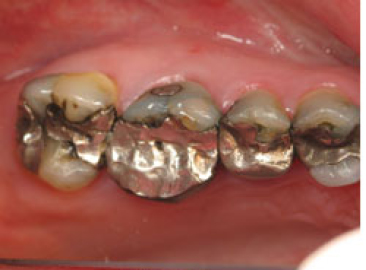

These are full crowns. Before shows old failing amalgam restorations.